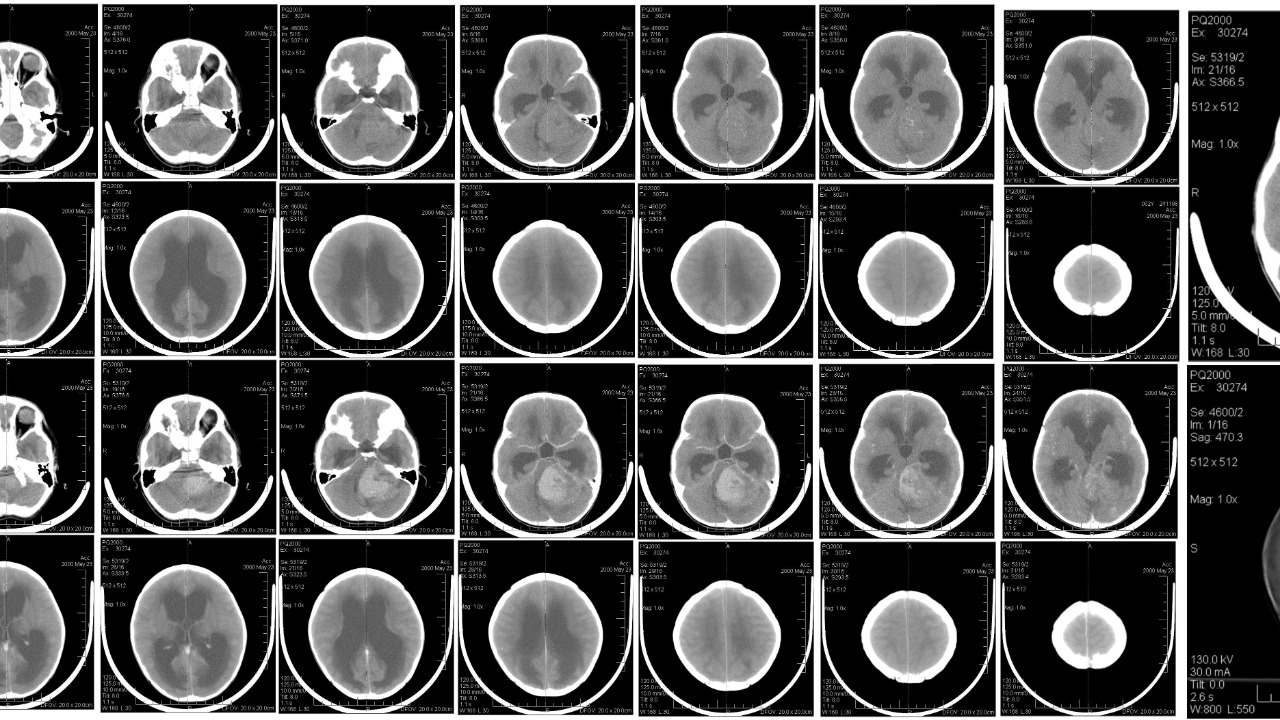

The research, led by a team of Swedish scientists, utilized advanced imaging techniques and methodologies to study the human brain. With this approach, the team was able to confirm the continuous production of new brain cells in adult humans. This discovery stands in stark contrast to the previously held belief that brain cell production, or neurogenesis, ceases in adulthood.

Neurogenesis is the process by which new neurons, or nerve cells, are formed in the brain. This process was previously thought to occur only in certain periods of life, particularly during prenatal development and early childhood. However, the recent discovery has shown that neurogenesis can continue well into old age, providing a new perspective on the brain’s capacity for growth and change.